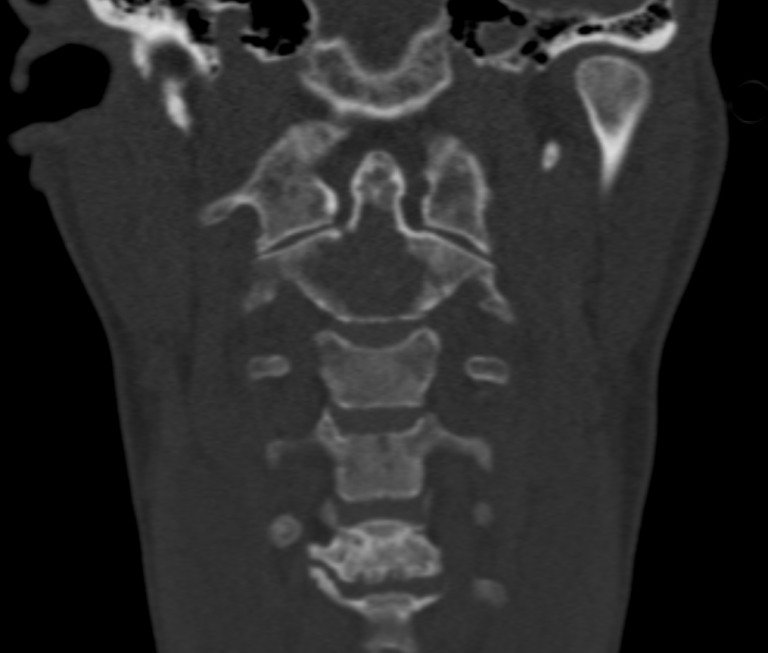

Les métastases osseuses sont fréquentes chez les patients atteints de cancer, touchant près de la moitié d’entre eux. Elles entraînent souvent douleurs et fractures dites « pathologiques », avec un impact majeur sur l’autonomie et la qualité de vie. Dans ce cas, la patiente souffrait d’une lésion ostéolytique à haut risque fracturaire de la dent de C2, nécessitant le port d’une minerve rigide, mal tolérée et très invalidante.

L’objectif de l’intervention était de stabiliser une zone fragilisée, à proximité immédiate de la moelle épinière, afin de réduire rapidement les douleurs, de permettre le retrait de la minerve et de restaurer l’autonomie de la patiente.

L’ostéosynthèse de la dent de C2 par voie percutanée latéro-cervicale est une technique innovante, peu répandue en France et non réalisée jusqu’alors en Auvergne. Elle a été démocratisée par des équipes lyonnaises et parisiennes, et se distingue par son efficacité clinique et un faible taux de complications.

L’intervention se déroule en salle de radiologie interventionnelle, sous anesthésie générale. Grâce à un guidage scanner et scopique en continu, une précision millimétrique est assurée à chaque étape :

Quelques images de l'intervention...